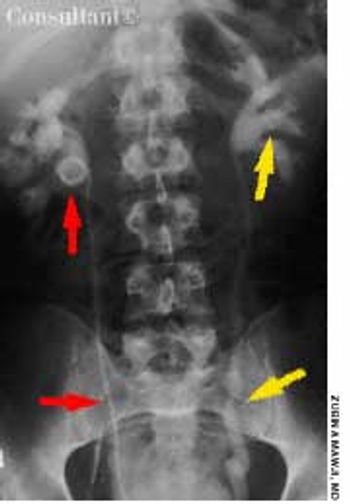

For 2 years, a 55-year-old woman's abdomen gradually enlarged; the pace of this growth had accelerated during the last 6 months. The patient, who had not seen a physician in 10 years, denied abdominal pain, nausea, vomiting, constipation, diarrhea, or any change in bowel habits. She had no shortness of breath or weakness. The patient reported no significant medical history, had no allergies, and took no medications. Her mother had died of ovarian cancer.